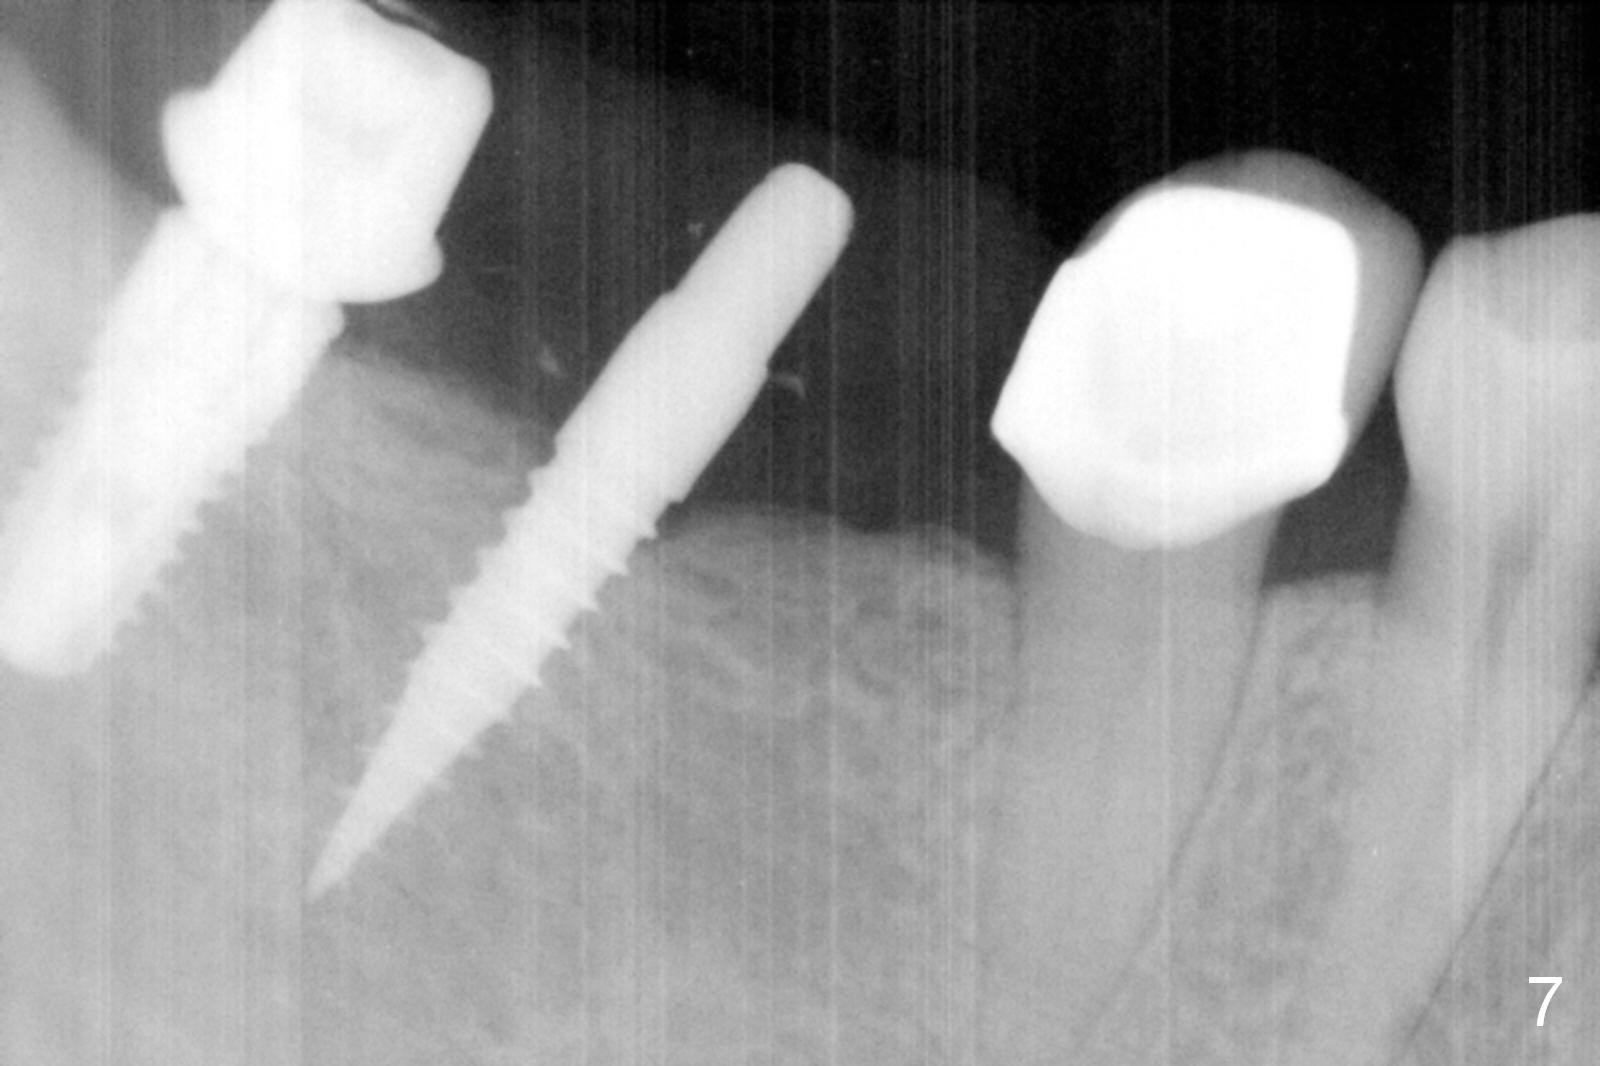

The patient returns for final restoration 3 months postop; bone resorption around the 1-piece implant is minimal (Fig.7). The definitive restoration is also splinted. The latter is further justified when the implant at #30 is found to be distal prior to cementation (Fig.8 *). It appears that implant spacing at the root level is more critical than parallelism, as compared to Fig.7. Let us improve this aspect. Bone loss around the implants remains minimal 7 months post cementation (Fig.9). It is the same 1 year 8 months post cementation (Fig.10), as compared to a cantilever FPD on the other side (Fig.11). The bone density around the implants at #30 and 31 increases 2 year 8 months post cementation (Fig.12).